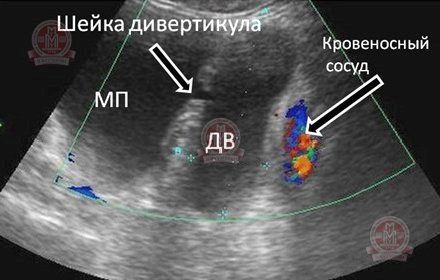

Рісунок№ 2 (УЗД) Типовий дивертикул (ДВ) сечового міхура - визначається чітке повідомлення (шийка дивертикула) між сечовим міхуром (МП) і дивертикулом.